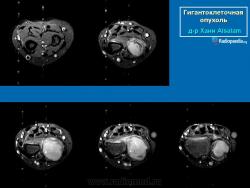

Гигантоклеточная опухоль.

Случай 8: МРТ